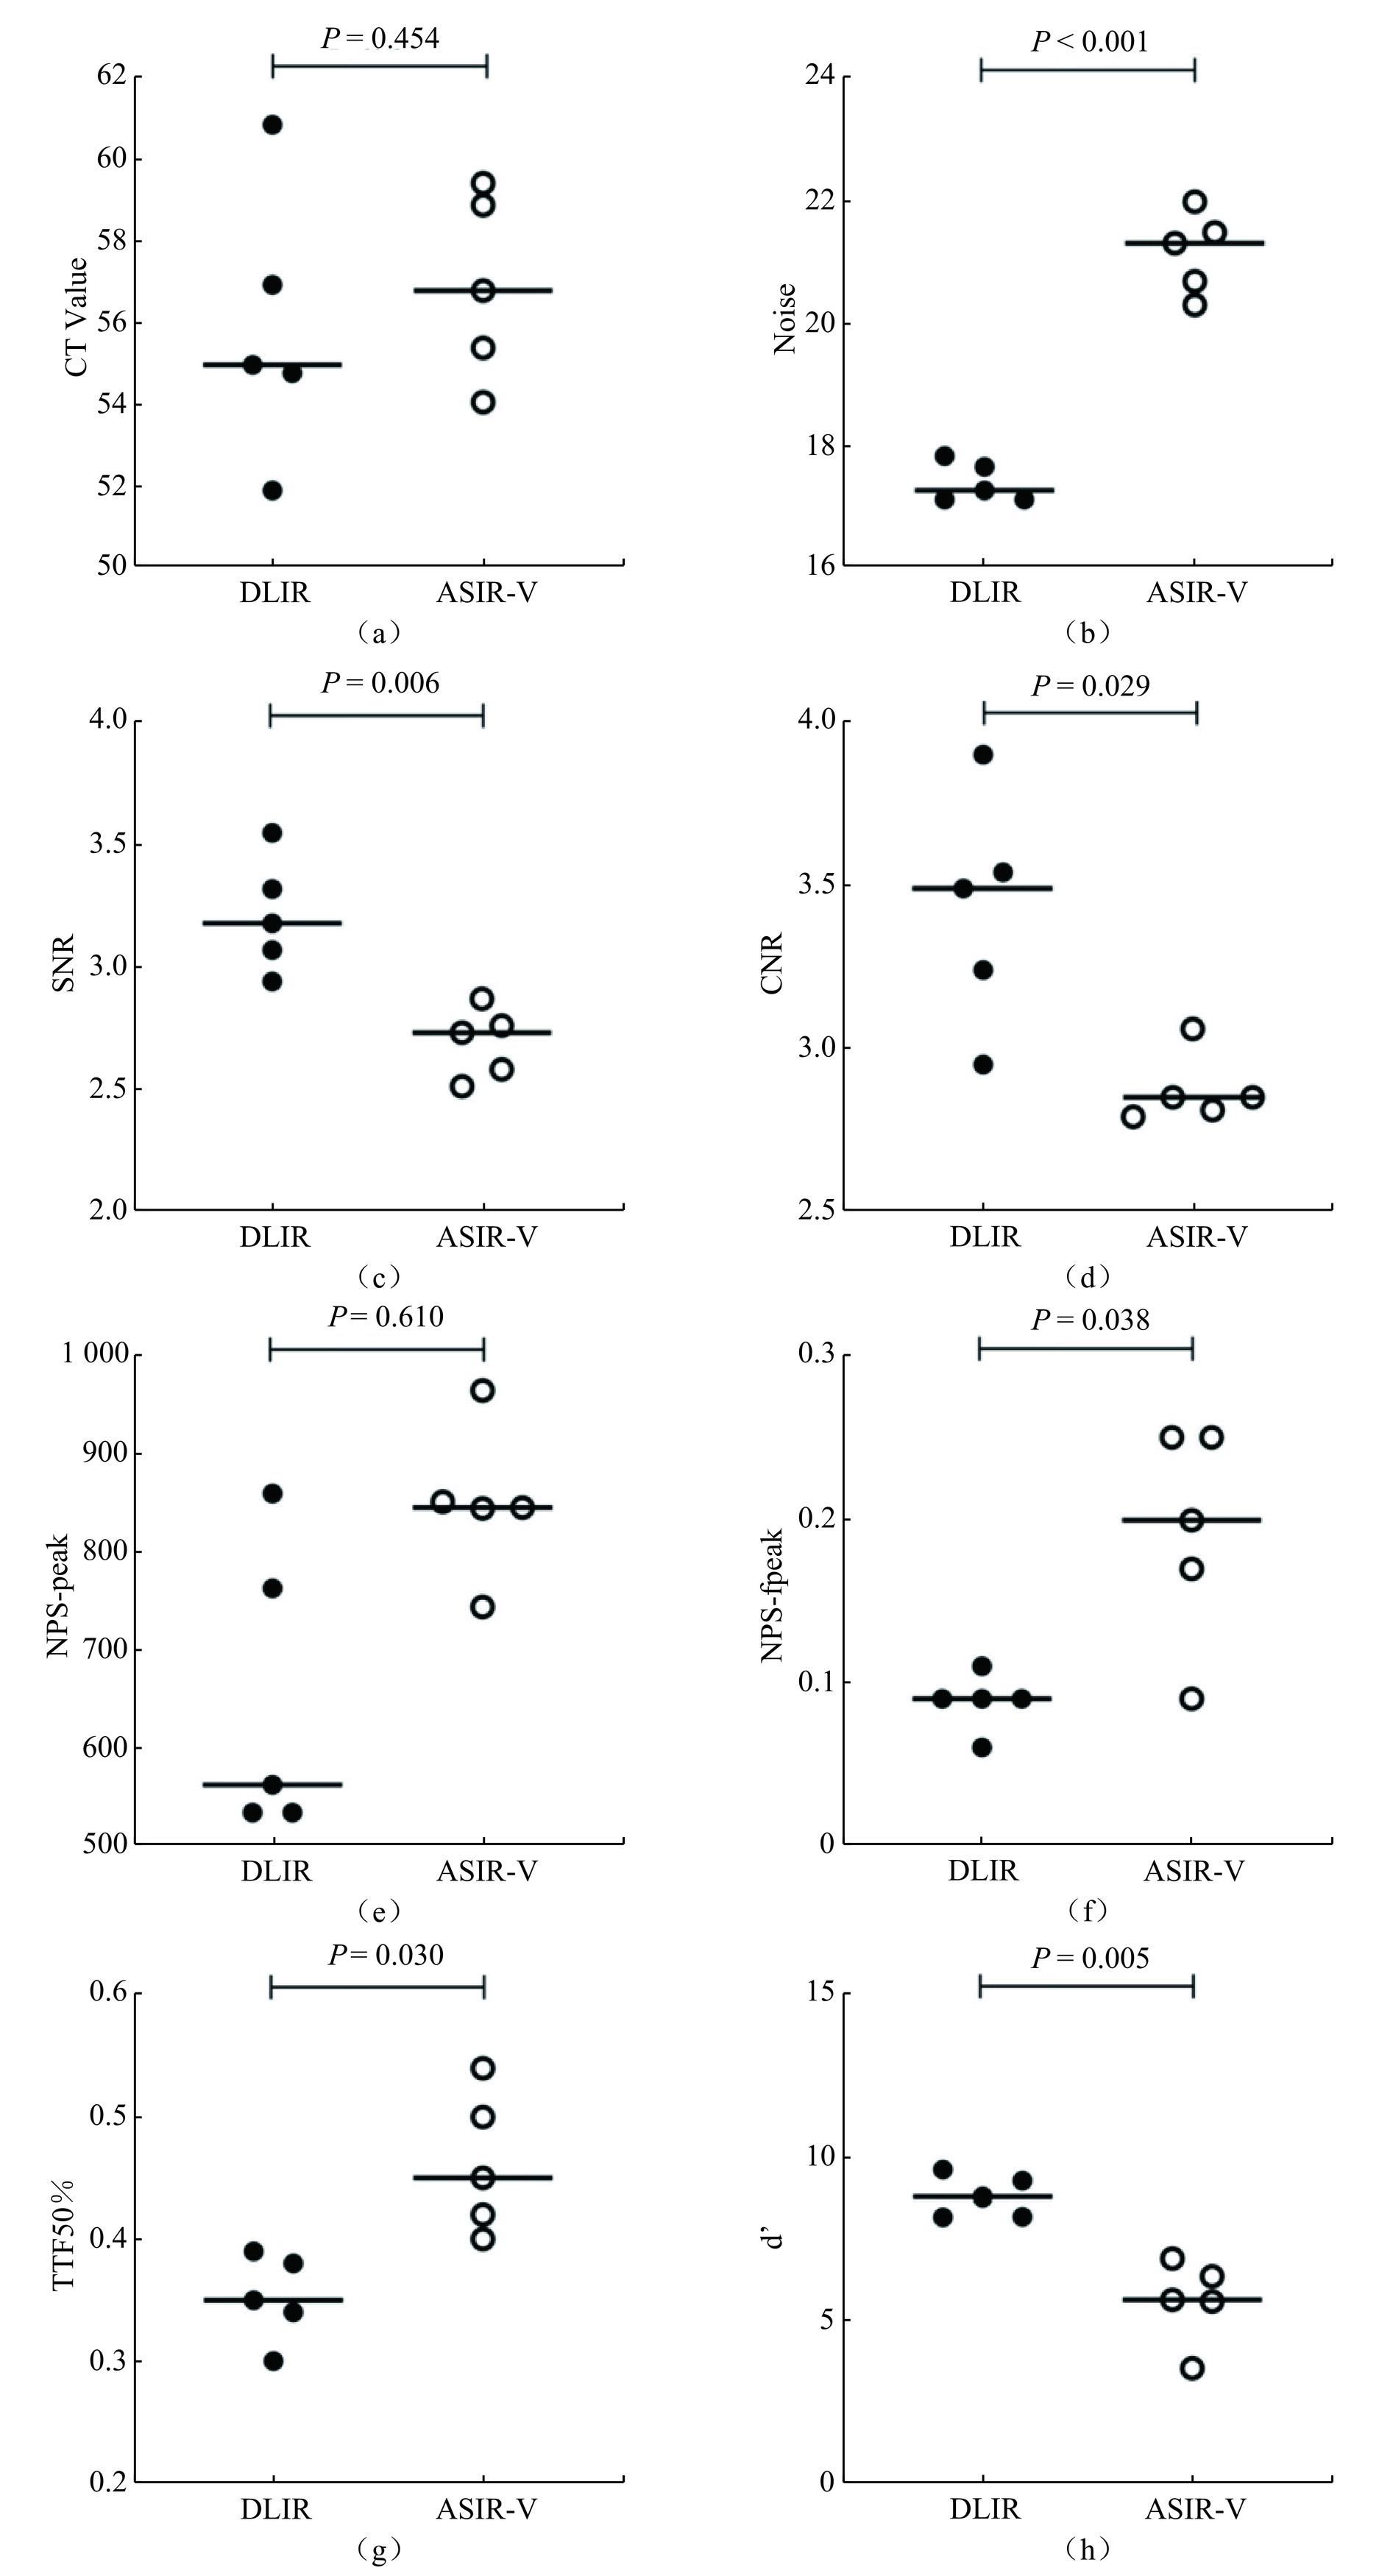

表2记录了在不同辐射剂量条件下,两种算法重建图像的CT值、噪声、SNR和CNR的平均值及标准差。图2展示了这些关键指标随辐射剂量变化的趋势。

表 2 在不同辐射剂量下,DLIR与ASIR-V算法重建图像的测量值比较Table 2. Comparison of measurements of reconstructed images by DLIR and ASIR-V algorithms at different radiation dosesCTDIvol/mGy CT value(P=0.001) Noise(P < 0.001) SNR(P < 0.001) CNR(P < 0.001) DLIR ASIR-V DLIR ASIR-V DLIR ASIR-V DLIR ASIR-V 30 62.66±3.17 62.06±3.55 11.12±0.69 17.19±1.05 5.65±0.38 3.62±0.19 5.3±0.12 3.69±0.15 20 55.91±2.08 57.58±2.81 12.15±0.34 19.39±0.33 4.61±0.22 2.97±0.15 4.09±0.26 3.2±0.17 15 55.94±1.70 56.91±2.27 13.66±0.55 21.17±0.67 4.1±0.16 2.69±0.14 3.89±0.26 2.87±0.11 10 55.74±2.18 57.71±3.17 15.18±0.30 24.19±1.06 3.67±0.10 2.39±0.17 3.83±0.33 2.63±0.27 7.5 55.35±2.32 59.86±3.34 15.79±0.57 26.37±1.50 3.51±0.20 2.28±0.24 3.78±0.14 2.44±0.17 4.5 55.88±3.31 59.94±4.77 17.41±0.32 29.33±0.91 3.21±0.24 2.05±0.20 3.42±0.35 2.18±0.30 在30 mGy的剂量下,DLIR的CT值高于ASIR-V。而在其它剂量下,DLIR的CT值均显著低于ASIR-V。

关于噪声水平,我们发现随着辐射剂量的增加,噪声水平逐渐降低。值得注意的是,在所有的剂量水平上,DLIR算法的噪声都显著低于ASIR-V。对于SNR和CNR,随着剂量增加,这两个指标呈上升趋势。在所有剂量条件下,DLIR算法的SNR和CNR均显著超过ASIR-V。这些数据统计结果表明,DLIR算法在多个关键性指标上均展现出一定的优势。

2.3 DLIR与ASIR-V重建图像的量化分析

表3展示在不同剂量辐射下,两种算法重建图像的NPS-peak、NPS-fpeak、TTF 50%和

$d' $ 的平均值及标准差。图3描绘这些指标随辐射剂量变化的曲线。表 3 在不同辐射剂量下,DLIR与ASIR-V算法重建图像的量化分析比较Table 3. Comparison of quantitative analysis of reconstructed images by DLIR and ASIR-V algorithms at different radiation dosesCTDIvol/mGy NPS-peak(P < 0.001) NPS-fpeak(P=0.379) TTF50%(P=0.61) $d' $(P < 0.001) DLIR ASIR-V DLIR ASIR-V DLIR ASIR-V DLIR ASIR-V 30 189.02±34.50 528.47±75.13 0.20±0.07 0.18±0.06 0.52±0.13 0.46±0.08 15.95±2.64 9.16±1.43 20 234.72±6.99 786.15±119.99 0.18±0.06 0.17±0.04 0.47±0.06 0.45±0.05 13.49±1.18 6.93±1.09 15 303.35±25.14 850.79±78.38 0.14±0.07 0.19±0.07 0.42±0.02 0.46±0.06 11.94±2.09 5.61±1.28 10 391.89±36.38 1168.32 ±84.180.15±0.05 0.15±0.04 0.4±0.02 0.44±0.11 9.64±0.72 4.94±0.64 7.5 418.12±63.66 1674.62 ±316.680.12±0.05 0.12±0.03 0.35±0.06 0.35±0.04 10.26±1.84 4.68±0.95 4.5 650.8±151.44 2385.55 ±474.440.09±0.02 0.12±0.04 0.35±0.04 0.30±0.06 8.81±0.63 4.43±0.40 观察曲线可知,NPS-peak随着辐射剂量的增加呈下降趋势。在任一剂量下,DLIR的NPS-peak均显著大于ASIR-V。对于NPS-fpeak,其值随着放射剂量的升高而增加。具体来说,在20 mGy和30 mGy的剂量下,DLIR的NPS-fpeak值大于ASIR-V;在7.5 mGy和10 mGy的剂量下,两者值相等;而在4.5 mGy和15 mGy的剂量下,DLIR的值小于ASIR-V的值(P=0.379)。TTF 50%随着辐射剂量的增加呈现上升趋势。在4.5、20和30 mGy的剂量下,DLIR的NPS-fpeak值大于ASIR-V;在7.5 mGy的剂量下,两者值相等;在10 mGy和15 mGy剂量下,DLIR的值小于ASIR-V。此外,

$d' $ 的值随着辐射剂量的增加而升高。在所有剂量水平上,DLIR的$d' $ 值均显著超过ASIR-V。综上所述,DLIR和ASIR-V在不同辐射剂量下的图像重建性能存在差异,这些差异反映了两种算法在不同辐射剂量条件下对图像细节的捕捉能力和整体图像质量的处理效果。

本研究的结果表明,在降噪、提高信噪比和对比噪声比方面,DLIR算法的表现优于ASIR-V。在不同辐射剂量下,DLIR和ASIR-V之间的CT值没有显著差异。值得注意的是,随着辐射剂量的增加,两种算法之间的CT值差异逐渐减小。此外,DLIR和ASIR-V的测量结果均显示,随着剂量的增加,噪声逐渐降低,并且DLIR始终低于ASIR-V。同时,SNR和CNR逐渐提高,DLIR在这方面始终优于ASIR-V。Van STIPHOUT等[4]的系统性综述通过总结16篇论著,也证明在腹部CT扫描中,测量CT值时DLIR和IR无明显不同,测量SNR和CNR时DLIR显著优于ASIR-V。

在图像的量化方面,随着剂量的增加,DLIR和ASIR-V两种算法处理下的NPS-peak均呈下降趋势,其中DLIR的降低幅度显著大于ASIR-V。然而,尽管两种算法处理下的NPS-fpeak和TTF 50%随剂量增加均呈上升趋势,但二者并未达到统计学上的显著差异。此外,随着剂量的增加,

$d' $ 在DLIR和ASIR-V两种算法下均有所增加,其中DLIR的增加幅度显著超过了ASIR-V。这与Greffier等[8,22]实验研究结果相一致,其通过两次体模实验证明了在增加辐射剂量的条件下,采用ASIR-V算法得到的所有NPS-peak值均高于DLIR,同时ASIR-V获得的所有$d' $ 值也均低于DLIR。本研究证实了DLIR在降噪方面的优势,相较于ASIR-V,DLIR在同是15 mGy的辐射剂量下能降低噪声64%,SNR增加64%,CNR增加36%,NPS-peak减少64%,其

$d' $ 值更是ASIR-V的两倍。即使在实验测得的最小剂量4.5 mGy条件下,相较于15 mGy的ASIR-V,DLIR噪声仍下降18%,SNR提高19%,CNR提高19%,NPS-peak下降24%,其$d' $ 值仍然是ASIR-V的1.6倍。DLIR能够在低对比度下优化肝脏病变的图像质量,比ASIR-V优化能力更强。在本研究中,我们针对上腹部CT扫描的典型临床应用,进行参数设置,其他研究发现即使在参数设置不同的情况下,DLIR相比于ASIR-V在图像优化能力上仍然表现更优秀[14,23]。